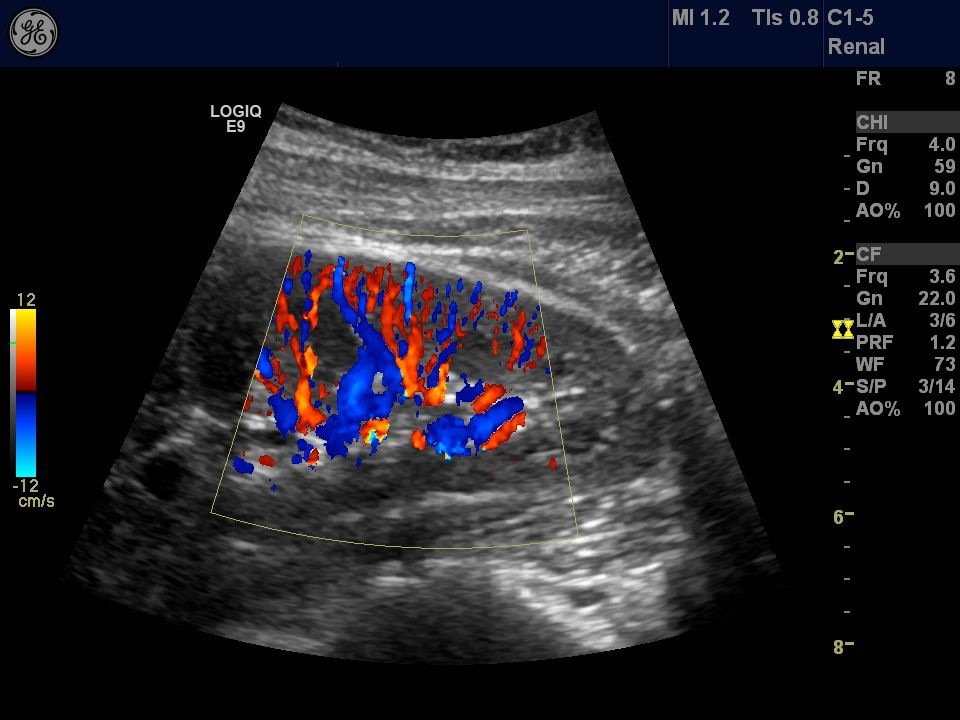

LOGIQ E9是國際上最高端的彩超設備之一,該設備操作靈巧,圖像清晰度高,配備瞭腹部、心臟、高頻、四維容積等4個探頭,采用多種成像技術,具有細微分辨率高、彩色血流充盈度好、對低速血流敏感度高等優點。可應用於腹部、心血管、婦產科、淺表器官、周圍血管、胃腸道等臟器疾病的超聲診斷,亦可開展超聲介入診斷與治療。

其二:容積導航技術 LOGIQ E9使軍事領域最前沿的容積導航、GPS技術在醫學領域得到瞭應用,容積導航技術是將實時超聲圖像與前次檢查獲得的CT、MR或PET圖像融合在一起,虛擬掃描以前的研究數據以匹配實時超聲圖像,將圖像並列或重疊起來進行比較,充分利用每個成像模式的優勢,通過雙定位器幫助醫生對患者的多個病變目標進行實時跟蹤,對腫瘤病灶進行標記追蹤,讓病變位置無處藏身,還可以實現神奇地在CT片上觀察血流!GPS標記的容積導航技術可以標記病灶的位置並幫助計數,並且通過對最佳穿刺角度的追蹤定位,避免碰到神經血管等結構,引導介入手術的完成,進一步提高穿刺診療的精確性與安全性。LOGIQ E9還可以使用超聲進行療效跟蹤,幫助患者減少CT用量,避免放射劑量。